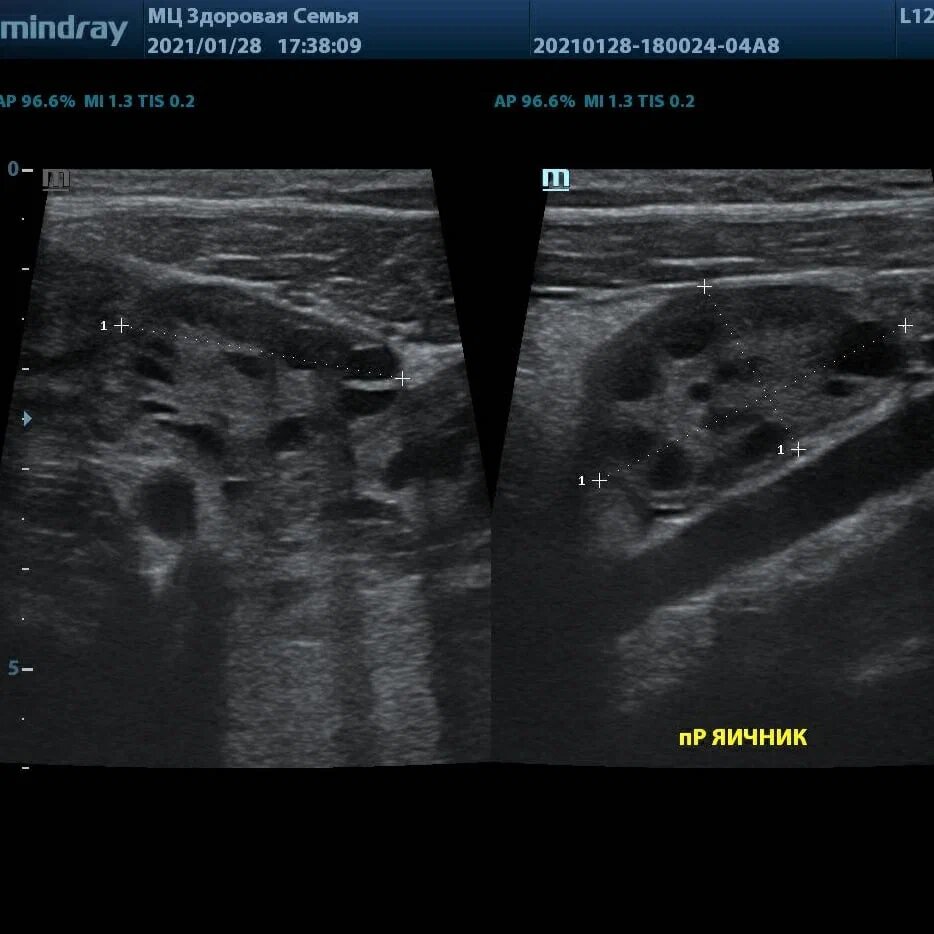

👍Да, вагинально можно посмотреть яичник в упор, на высоких частотах. А можно не найти его вообще. У той же пациентки можно найти яичник даже линейным датчиком трансабдоминально при слепой трансвагинальной зоне.

🖼️Пример из практики Константина Князева: вагинальное сканирование дало только изображение матки, яичники не найдены. При абдоминальном сканировании найдены оба яичника. Левый увеличен более 10 см в длину, сосудистый рисунок скудный, имеет жидкостное аваскулярное включение. Сопровождается субфебрильной температурой и небольшим выпотом вокруг яичника. Отправлена специалистам. Инфильтрат? Перекрут?

👨‍⚕️Если есть возможность использовать разные доступы - используй их всё. Исследование должно дать результат.